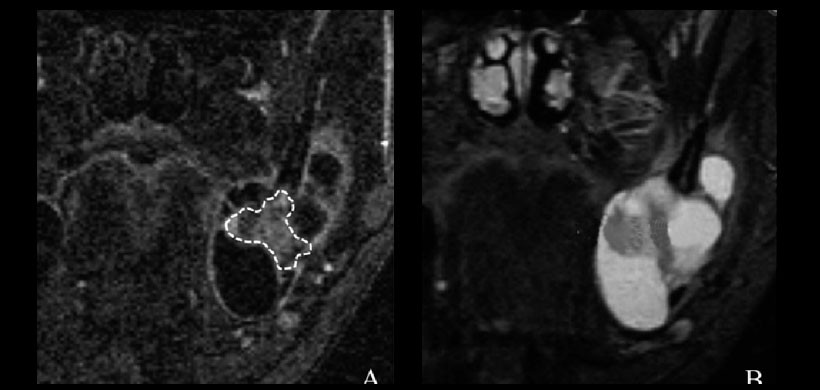

Figura 2: Ameloblastoma que se extiende desde la mandíbula izquierda hasta la rama en un varón de 42 años. (A) La región de interés (línea discontinua), que evitaba las partes quísticas del tumor, se marcó en una imagen dinámica coronal. (B) La imagen de recuperación de inversión de TI corta